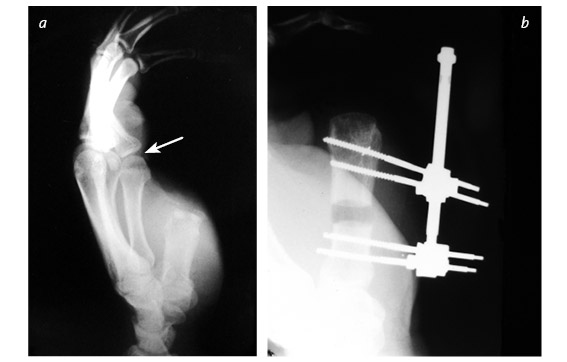

Кистевые хирурги [37] все это знают и при необходимости будут трудиться ночь напролет, лишь бы вернуть поврежденный палец на место. Даже полностью отделенный большой палец можно успешно приживить – реплантировать. Его чувствительность, подвижность и сила никогда полностью не восстановятся, но так, безусловно, лучше, чем вообще без пальца. Если восстановить или приживить эту важнейшую часть кисти невозможно, ее реконструируют. Существует три основные методики, которые я условно называю «упросить», «одолжить» и «украсть». В первом случае хирург и пациент как бы упрашивают обрубок большого пальца вырасти в длину. С обоих концов оставшейся кости хирург вставляет поперечные стальные шпильки, прикрепляет эти шпильки к стальной раме и разрезает кость между ними. Пациент каждый час поворачивает небольшую ручку этого приспособления, напоминающего аппарат Илизарова, и по чуть-чуть увеличивает промежуток между фрагментами кости. Процедура длится от шести до восьми недель. Кость и окружающие ее мышцы, сухожилия, нервы и кожа едва ли понимают, что их растягивают: для них это просто какой-то очень быстрый рост, и им надо успеть. Когда большой палец вновь обретает рабочую длину, хирург заполняет промежуток костным трансплантатом. Преимущество такого способа удлинения в том, что не приходится ничего «одалживать» или «красть». Однако не все так радужно: ноготь и отсутствующие суставы большого пальца уже не вернуть. Другие четыре пальца – указательный, средний, безымянный и мизинец – работают аналогично друг другу, и потеря одного из них имеет гораздо меньшие последствия, чем потеря большого пальца. На этом и основана вторая методика реконструкции большого пальца. Как вы думаете, что приходит в голову хирургу, если незаменимого большого пальца не хватает, а рядом расположились четыре его недостаточно занятых дружка? Разумеется, позаимствовать один из них! Обычно выбирают самый близкий – указательный. Хирург укорачивает его и разворачивает в положение большого. Эта процедура сложнее, чем удлинение остатка пальца, рука становится четырехпалой, зато новый большой палец будет иметь ноготь, и восстановление пройдет быстрее. ![]() ![]() В данном случае культя большого пальца была постепенно увеличена до длины, достаточной, чтобы сжимать и хватать. До лечения большой палец заметно короче – для сравнения стрелкой отмечен первый сустав указательного пальца (a). Во время первой операции врач ставит дистракционное устройство, разрезает кость и осторожно раздвигает ее концы (b). Расстояние между фрагментами кости постепенно увеличивают (на это уходит от шести до восьми недель), наращивают кожу, сухожилия, нервы и кровеносные сосуды (c). После этого в расширенный промежуток кости пересаживают трансплантат из бедра (d). Когда пересаженная кость заживает, работоспособность пальца восстанавливается, и аппарат снимают. Стрелкой показана новая длина по сравнению с исходным состоянием (e) ![]() Реконструкция большого пальца путем укорачивания и разворота указательного пальца: состояние до операции (a) и после нее (b, c) Бывает, что на одной кисти руки не хватает сразу нескольких пальцев или пациенту нужны все пальцы. В этих случаях «пригласить соседа» не получится. Если не удается «уговорить» культю вырасти, хирург может прибегнуть к «краже». Жертвой становится стопа. Большие пальцы ноги по форме почти идентичны своим собратьям на руках, поэтому именно они чаще всего идут в дело – вот только место преступления выглядит довольно неприглядно. Если похитить второй палец ноги, замена из него получится совсем тощая, зато ступня будет иметь аккуратные очертания. Такой вариант обычно выбирают в странах, где в помещении принято снимать обувь. На способность ходить и бегать отсутствие первого или второго пальца ноги почти не влияет. ![]() У этого пациента большим пальцем ноги заменили большой палец левой руки, утраченный в результате травмы. Стопа после операции полностью сохранила функциональность Операция по пересадке пальца с ноги на руку длится от пяти до десяти часов и требует прекрасного владения навыками микрохирургии. Хирург определяет нервы, артерии, вены и сухожилия пальца стопы, изолирует их и отрезает вместе с костью. Ампутированный палец переносят на руку и стыкуют аналогичные ткани между собой. Хирург обычно крепит кость пересаженного пальца к оставшейся в руке кости с помощью стальных штырей. Диаметр кровеносных сосудов – от полутора до трех миллиметров: их необходимо точно соединить практически невидимыми швами, ведь кровь должна двигаться по сосудам, не просачиваясь наружу. Когда кровообращение возобновится, концы кости будут спокойно заживать, не понимая, что стопа перепуталась с кистью руки. Пройдут месяцы, в пересаженный палец врастут новые нервные волокна, и чувствительность восстановится. По-английски получившуюся комбинацию иногда называют thoe [38]. * * * Помните? В период своего зарождения в XVIII веке ортопедия в основном занималась детьми. Доктора лечили деформации скелета, возникшие вследствие перенесенных заболеваний (туберкулеза, полиомиелита и рахита), исключительно неоперативными методами. Со временем эти болезни ушли в прошлое, появилась общая анестезия, возросли требования к стерильности, операции стали значительно безопаснее, а методы лечения усложнились. Один из таких методов – использование аппарата Илизарова для увеличения роста человека. Итальянские хирурги-ортопеды познакомили страны Запада с разработанными Илизаровым методами лечения переломов и начали применять их в борьбе с низкорослостью. Кое-кто считает, что это лишь косметическая процедура. Другие возражают, что она совершенно необходима для общего хорошего самочувствия тех, чей рост явно ниже нормы. Изначально аппараты устанавливали снаружи на обе ноги: большеберцовые кости распиливали посередине, а затем в течение нескольких месяцев растягивали на пять – восемь сантиметров. Следовали месяцы восстановления: удлиненные кости должны стать достаточно прочными, чтобы выдержать массу тела человека. Сегодня пациенты могут выбрать и другой вариант – удлинить бедренные кости. К сожалению, руки после такой процедуры будут выглядеть непропорционально короткими, поэтому некоторые пациенты не останавливаются на достигнутом и удлиняют плечевые кости. Места установки спиц должны быть тщательно очищены и продезинфицированы – через них в кость могут проникнуть кожные инфекции. Если заражение все-таки произошло, необходимо сразу начать агрессивное лечение, в противном случае одна серьезная проблема сменится другой. |